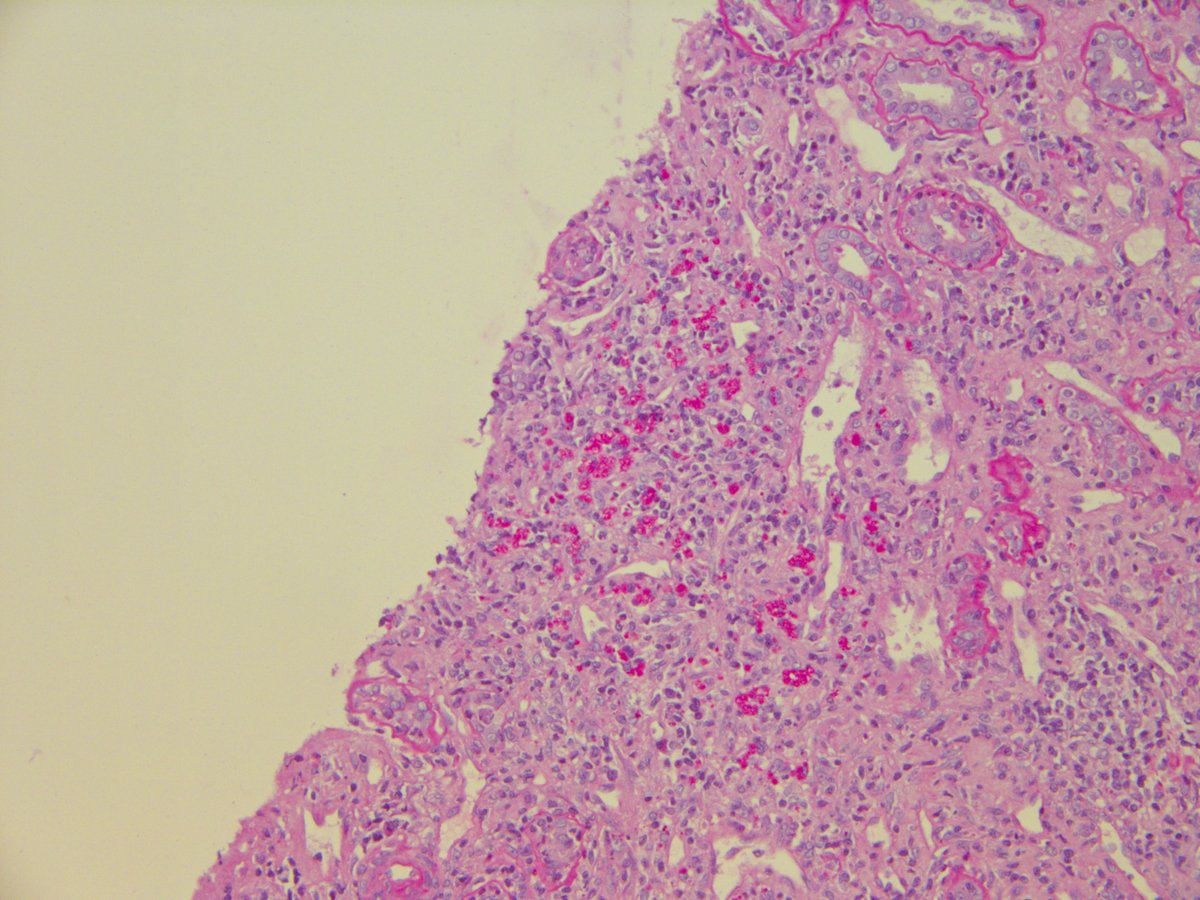

Interesting and somewhat subtle liver case. Middle aged, fatigue, cytopenias, elevated ALT, AST, AlkPhos. Non-targeted liver biopsy. Any ideas or suggestions for further workup?

#liverpath#GIpath#pathology pic.twitter.com/17gcK61BQ8